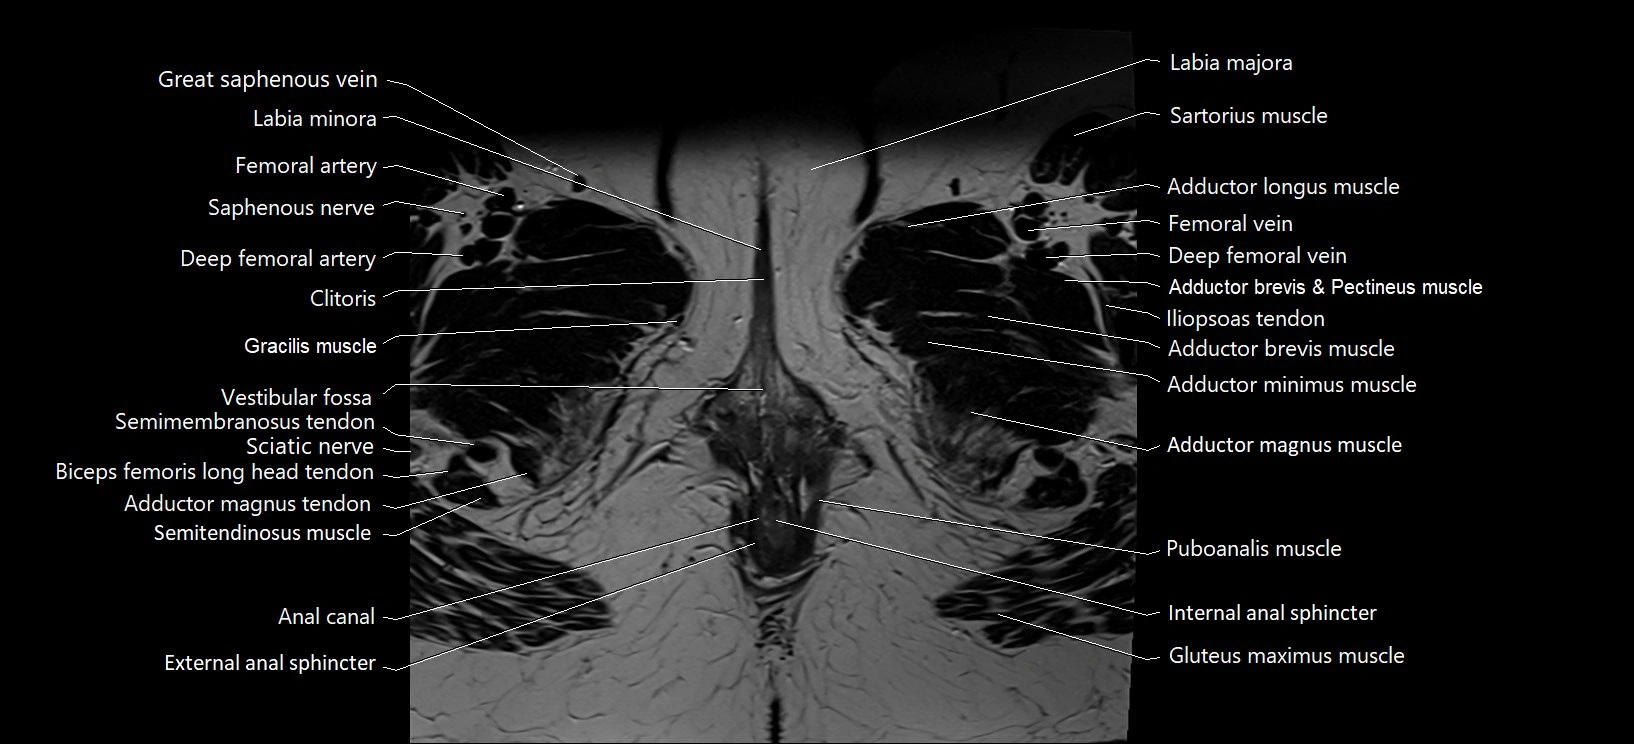

- Anal canal

- Bulbospongiosus muscle (Female)

- Clitoris

- External anal sphincter

- Gracilis muscle

- Internal anal sphincter

- Ischiocavernosus muscle (Female)

- Labia majora

- Labia minora

- Puboanalis muscle

- Saphenous nerve

- Sciatic nerve

- Semimembranosus tendon (proximal)

- Vestibular fossa